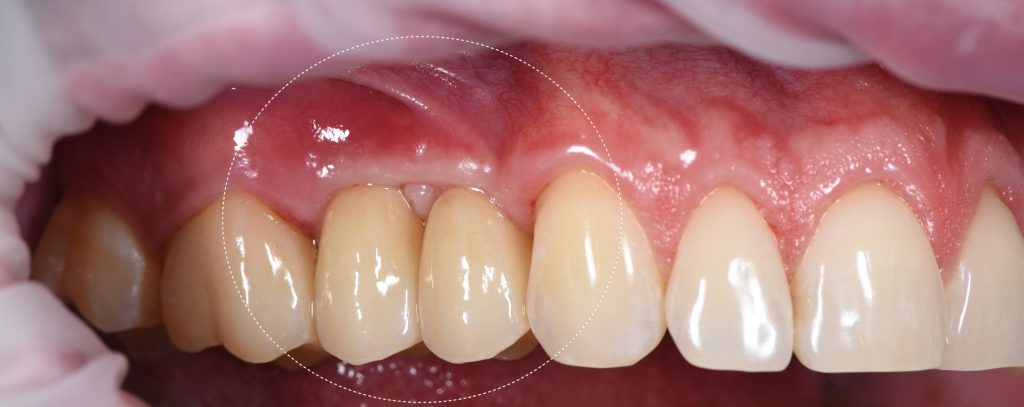

Сформирован желаемый профиль прорезывания